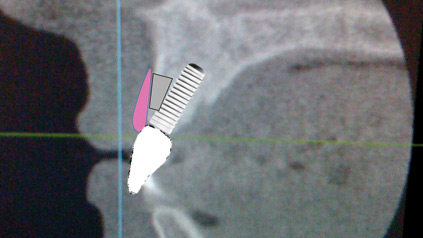

To Guide Or Not To Guide: There Is No Question! A Complete Digital Workflow For Guided Implant Surgery Using CEREC Guide 2

Rihal-sample-of-medium-size-key-sets-for-nobel-implants2 alternate text for this image

The evolution of implant treatment planning has changed over the course of history. From the start, implant dentistry was considered to be surgically driven. Our current standard of care is three-dimensional placement of implants being gingivally driven. By using the latest in intraoral imaging, we can now virtualize the ideal gingival zenith position and appearance … Read more